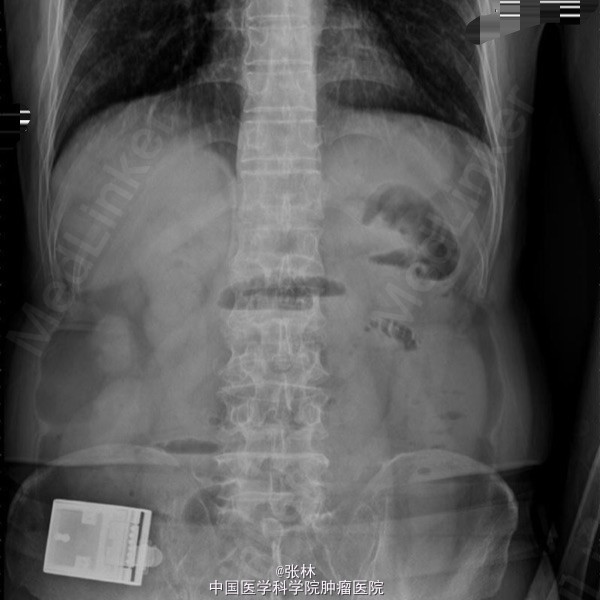

男性,72岁。 主诉:突发腹痛、腹胀伴呕吐1天。 现病史:患者1天前无诱因感全腹部疼痛,呈阵发性绞痛,无放射痛,疼痛开始不剧,伴有畏寒,呕吐胃内容物1次,量约30ml。遂到我院门诊就诊,考虑为急性胃肠炎,予抗炎、解痉护胃等支持治疗,症状未见好转,并进行性加重而入住我科。 专科检查:全腹稍胀,未见肠型及蠕动波,无上腹搏动。腹软,中下轻压痛,无反跳痛。全腹未及肿块,肠鸣音活跃,7次/分。 术中所见:探查见异物位于回肠距回盲部约50cm,大小约8*3*2cm,堵塞肠管,近端肠管充血水肿明显,肠管扩张最大处直径约8cm,未见浆膜层破裂损伤等,系膜无扭转,有少许渗液,探查全部小肠未及肿物腹腔内可见中等量黄色积液,稍浑浊,网膜及腹膜有少量脓苔。洗净腹腔内积液,于肿物边缘对肠系膜缘纵行切开约2cm,取出异物,为半个大小约8*3*2cm的冬菇。